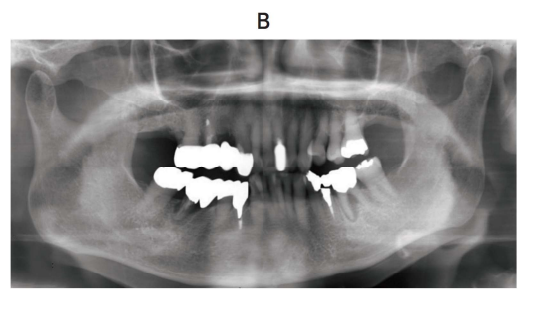

116回 D-77

56 歳の女性。下顎左側臼歯部の痛みと歯の動揺を主訴として来院した。 2 か月

前から疼痛を自覚し、次第に動揺してきたという。下顎左側臼歯部に 42 × 20 mm

大の腫瘤を認め、生検の結果は扁平上皮癌であった。FDG-PET/CT で遠隔転移を

認めなかった。初診時の口腔内写真(別冊No. 31A)、エックス線画像(別冊No. 31

B)及び FDG-PET/CT(別冊No. 31C)を別に示す。

TNM 分類(UICC2017)はどれか。 1 つ選べ。

解答:d

解説:

T:癌の広がり

N:リンパ節転移 N0:なし N1:3cm以下。一つのリンパ節に転移。癌と同側 N2:6cm以下。2つ以上のリンパ節の転移。癌と同側 N3:6cm以下。リンパ節の転移。癌と同側と反対側に。

M:遠隔転移

下顎左側臼歯部に 42 × 20 mm⇒4cmをこえているのでT4a

遠隔転移なし⇒M0

FDG-PET⇒癌の広がり具合、転移場所が分かる検査。今、左側(癌と同じ側)に複数リンパ節転移しているのが分かる。そして、6cm以下なのでN2b

T4bほど浸潤していない。